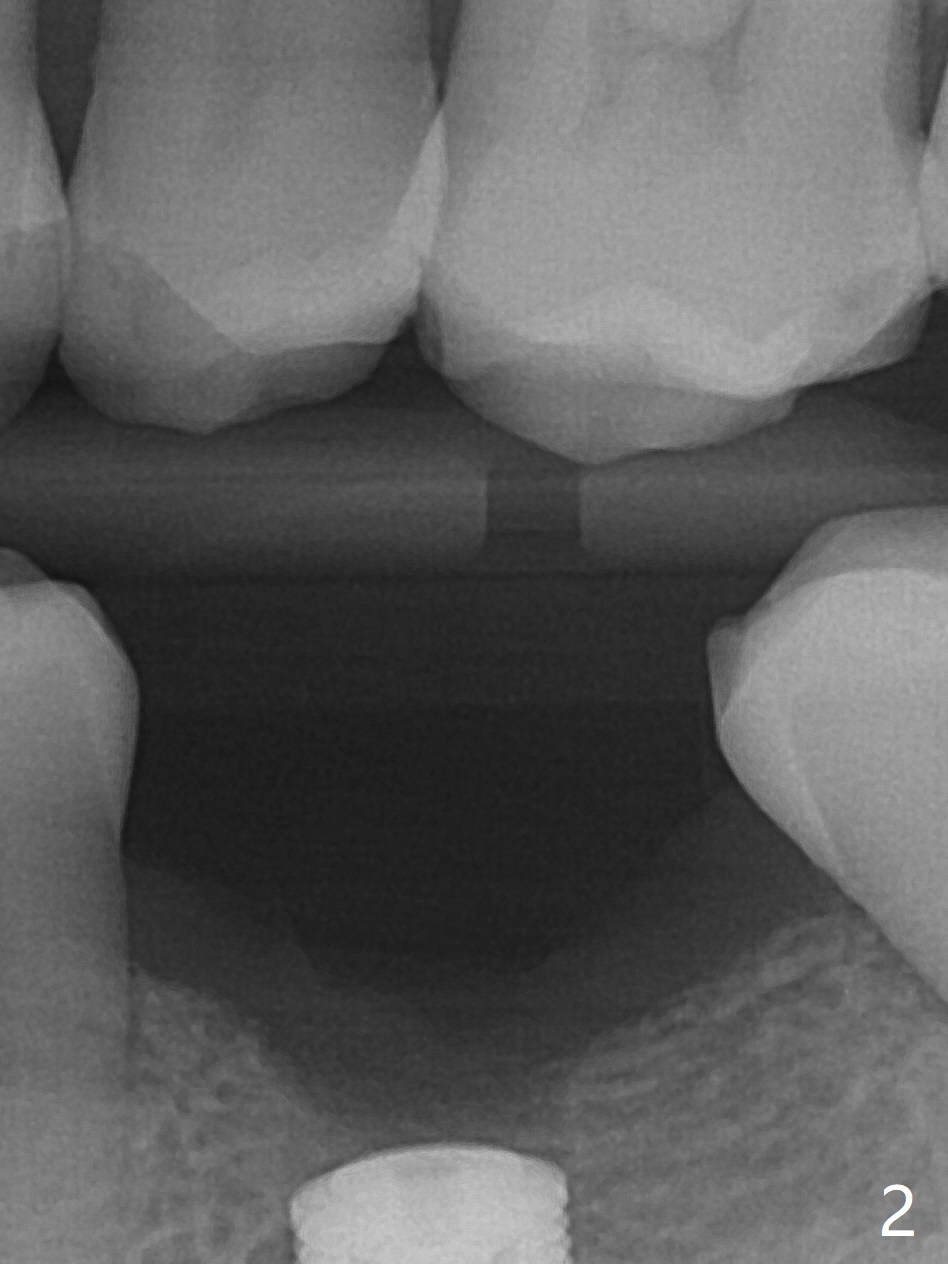

50岁男,左下6牙槽骨宽,但是骨密度低。开始使用导板和小钻头,植体(5x10毫米)扭力大,改用正常钻头,扭力仍高,使用功螺纹后,扭力~35Ncm;使用6毫米profile drill后,放置6x4(2)毫米愈合基台,后者好像与近中牙槽嵴接触(图一:*)。取出基台不顺利,接着放置5x5(3)毫米基台,无法拧紧,取出时,把植体带出来。最后把植体推入钻洞,没有任何扭力,放置愈合帽和Osteogen Plug,缝合(图二,三),牙周敷料,但愿能愈合。在骨质密度低时,放置不合适基台(太宽,太短),可能造成植体松动,脱落,失败。术后十二天牙周敷料脱落,伤口正在愈合(图四(曾经使用环形刀))。术后四个月植体仿佛已经整合(图五),切开放置6.2x5(3)毫米愈合基台,好像与近中牙槽嵴接触太紧(图六)。12天后放置修复基台,似乎就位(图七),其实我们使用取模帽放置基台,非常容易,取模也方便。基台牙冠就位也容易(图八)。螺丝拧紧25Ncm/厂家建议35Ncm。